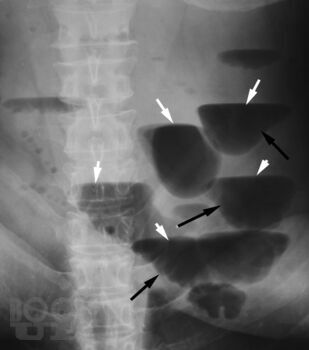

Учебно-методическое пособие разработано для подготовки к занятиям по лучевой диагностике заболеваний органов ЖКТ. В пособии рассматриваются всесторонние аспекты методов лучевой диагностики при подозрении на острое хирургическое заболевание органов ЖКТ, в частности кишечную непроходимость, прободение полого органа, нарушение брыжеечного кровообращения и др.